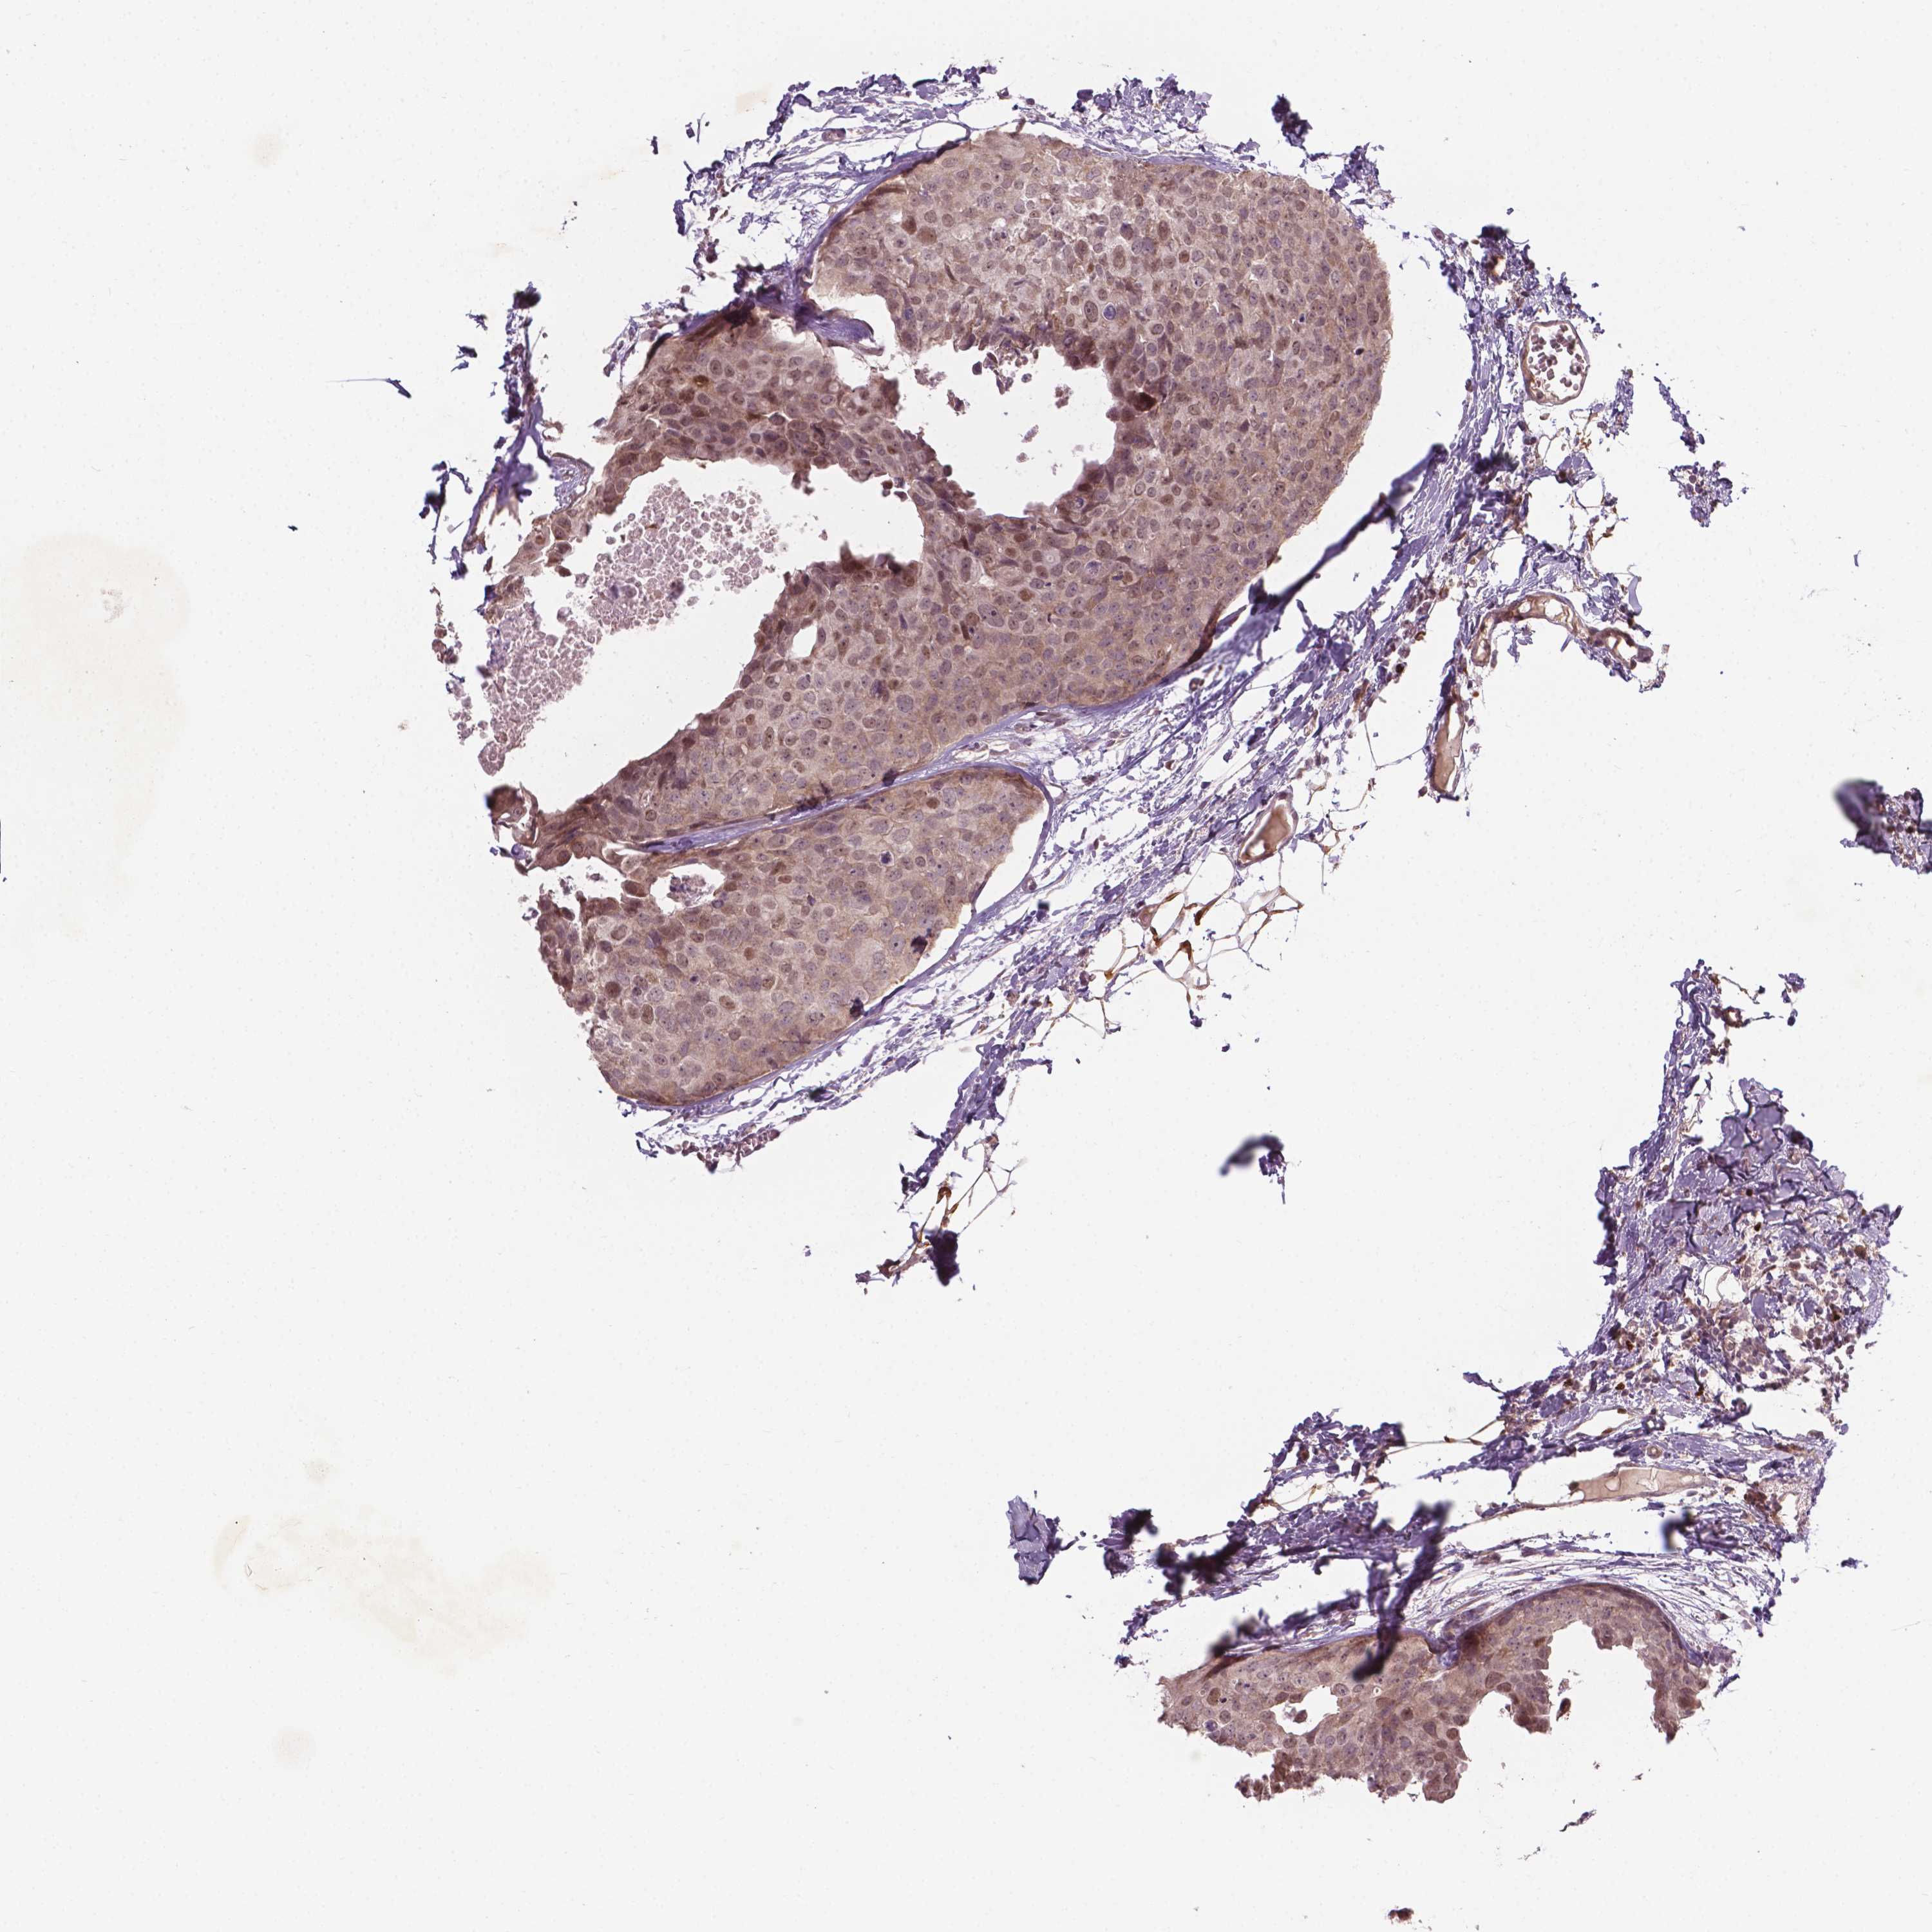

BRCA TCGA BRCA VALIDATION PROTEIN EXPRESSION

ANTIBODIES

AND

VALIDATION